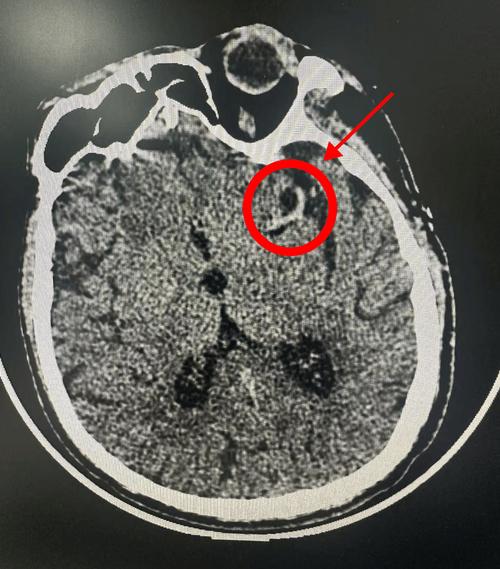

后期梗死灶形成: 当脑缺血持续超过6-12小时后,缺血中心的脑细胞开始坏死、水肿,这时在CT上会表现为低密度灶(颜色比周围正常的脑组织要暗),这个区域就是坏死的脑组织。

(图片来源网络,侵删)